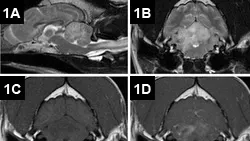

The patient was admitted to the hospital for an MRI, cerebrospinal fluid (CSF) analysis, and testing for possible infectious disease. Results of preanesthetic CBC, chemistry panel, total thyroxine (TT4), and urinalysis were unremarkable. The MRI (Figure 1) revealed lesions throughout the brain, most prominently in the cerebellum, brainstem, and cranial cervical spinal cord. Multifocal T2-weighted hyperintensities of the cerebellum, medulla oblongata, and cranial cervical spinal cord were noted. These regions were generally hyperintense on fluid-attenuated inversion recovery (FLAIR) images and isointense on T1-weighted images and displayed moderate, patchy contrast enhancement. Excessive contrast enhancement of the meninges around the brainstem and cerebral hemispheres was also noted. In addition, MRI also showed C2–3 intervertebral disk protrusion with mild-to-moderate spinal cord compression, which was considered an incidental finding.

Figure 1. MRI of the brain: Sagittal T2-weighted images reveal multifocal, hyperintense intraaxial lesions of the brainstem, cerebellum, and cranial cervical spinal cord (A). Axial T2-weighted images at the level of the cerebellum showed marked hyperintensity of the cerebellum and right lateral medulla oblongata (B). The lesions were isointense to hypo-intense on precontrast T1-weighted images (C) and displayed moderate, patchy contrast enhancement (D).